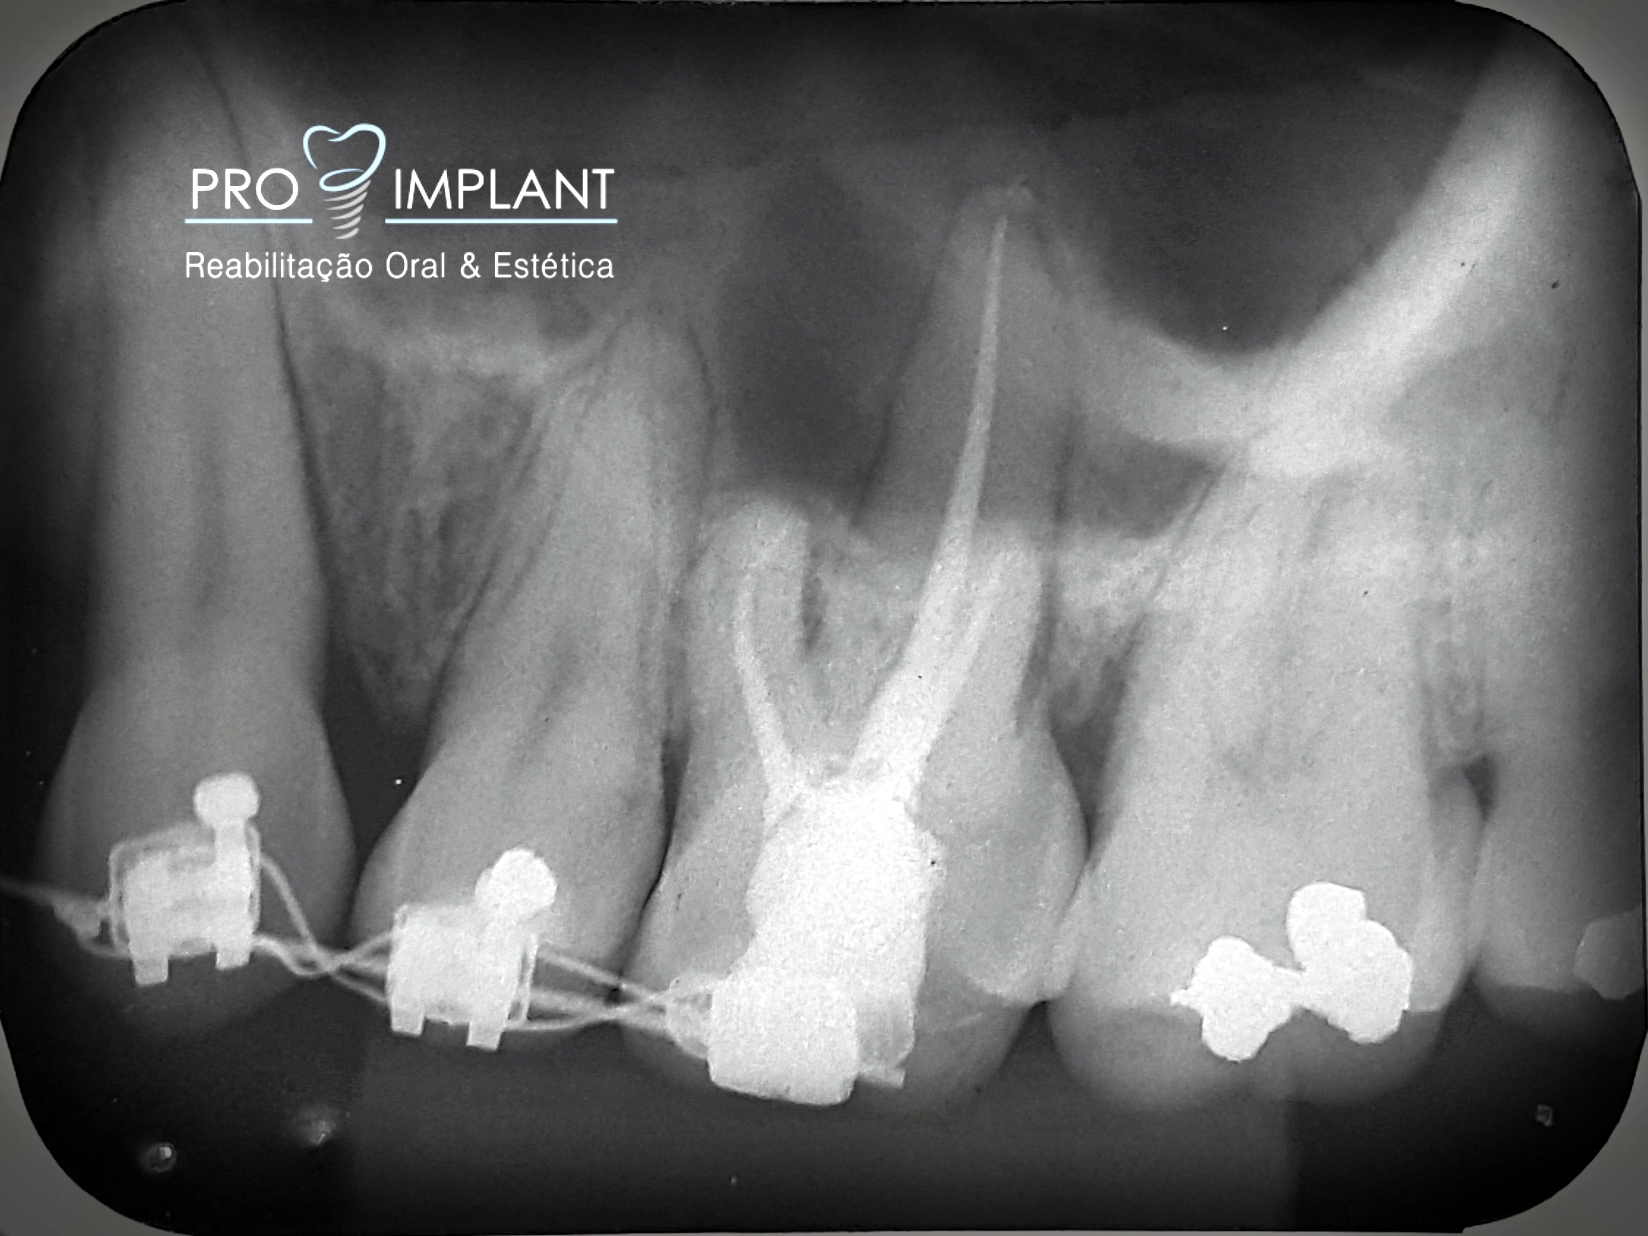

FOTOS

Endodontia